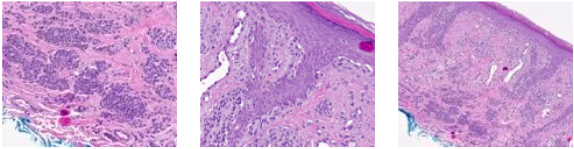

Lesion showed compound proliferation of melanocytes. In the epidermis, there were also many single melanocytes with limited pagetoid scatter. In the dermis, there were many nests, cords, and small syncytia with maturation or pseudo-maturation. Scattered inflammation was apparent. PRAME expression was absent. Due to the difficulty of the case and suspicious features, outside consultation was requested. p16 staining was performed and was diffusely positive. Neither PRAME nor p16 staining demonstrated biphasic reactivity as can be seen in the setting of melanoma. The consulting pathologist's impression was that the lesion was an extreme compound acral melanocytic nevus. No treatment recommendation was provided.